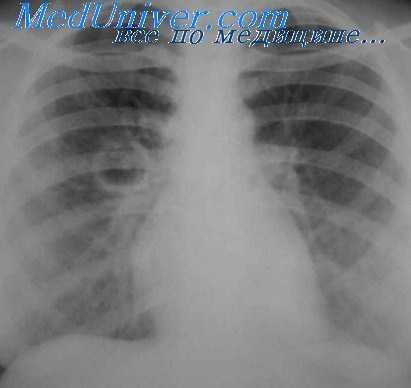

Каверозный, фиброзный туберкулез

Каверозная форма туберкулеза означает образование в легком участка некроза ткани — каверны, которая имеет вид полости, заполненной жидкой массой.

Некротический процесс может сопровождаться замещением нормальной ткани соединительной (фиброзной). Такие изменения называются цирротическими и обычно сопровождаются легочными кровотечениями.

Обширный процесс при туберкулезе служит показанием к удалению легкого.

У абсолютного числа больных поражение в легком было распространенным, свидетельствующее о далеко зашедшем тяжелом процессе тотального повреждения одного легкого и у 93,5% изменение в другом (в том числе у 26 каверна в остающемся легком).

Таким образом, характер патологического процесса и его распространенность указывали на необратимость изменений, где нельзя было рассчитывать на излечение с помощью комплекса терапевтических мероприятий.